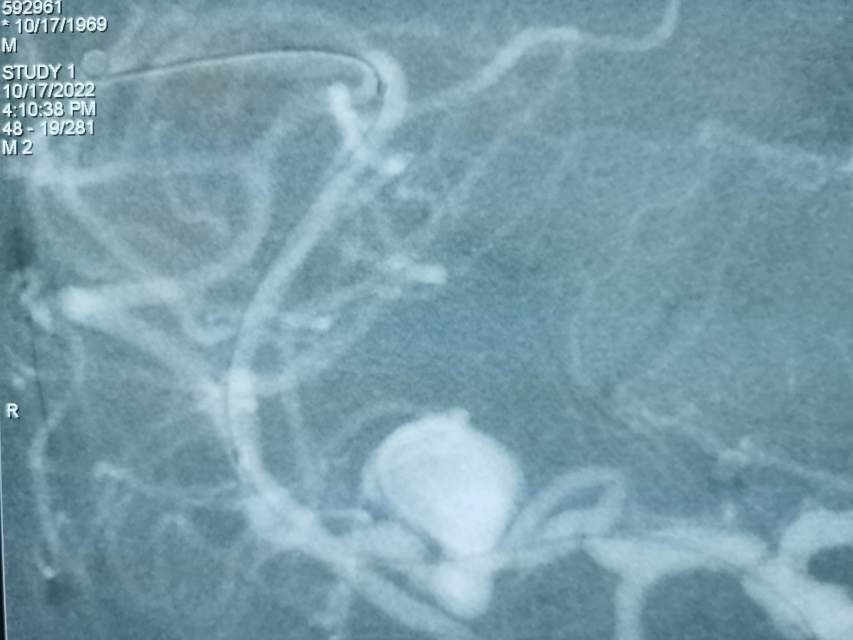

福建中年女性,近期在外查出“颅内动脉瘤”,经推荐转来我院诊治。患者的颈内动脉通路迂曲,动脉瘤也位置奇特,解剖复杂,动脉瘤远近段的血管弯弯绕绕,重重叠叠,眼花缭乱,难以兼顾找到最佳位置。最终克服困难,将“基底型”动脉瘤改变为“侧壁型”动脉瘤,顺利给予治疗……